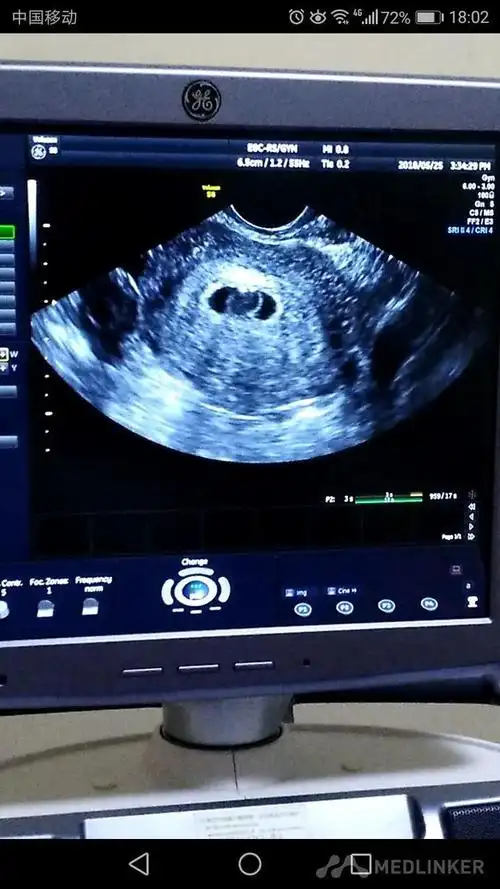

诊断 处理发病以来,未用药,二便正常,无腹痛随访 讨论停经43天,阴道不

会在20mm左右,根据发育的情况会有差别胚胎的发育,3040天形成的是胎囊

看清楚已生男孩阴超孕囊图片长这样图解茄子型胎囊数据

其实看孕囊很准 四十天孕囊圆形百分百女孩

怀孕四十多天做的b超看孕囊长宽高能看男女?